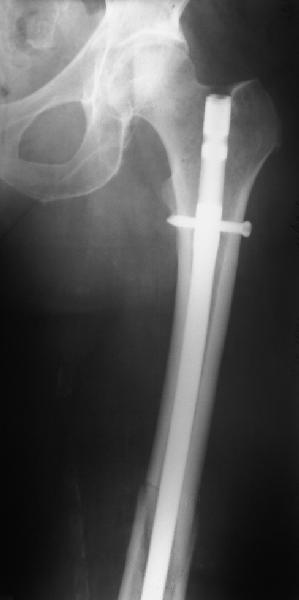

В приложении - недавний перипротезный перелом.

Методичка по закрытому интрамедулярному остеосинтезу при дистальных переломах бедра тут.

При низких переломах, когда клин опускается к суставу, пусть и без смещения внизу, мы опасаемся за стабильность когда есть шанс ввести дистальные блокировочные винты в клин.

Спасибо за ваш случай, очень элегантное решение перипротезного перелома.